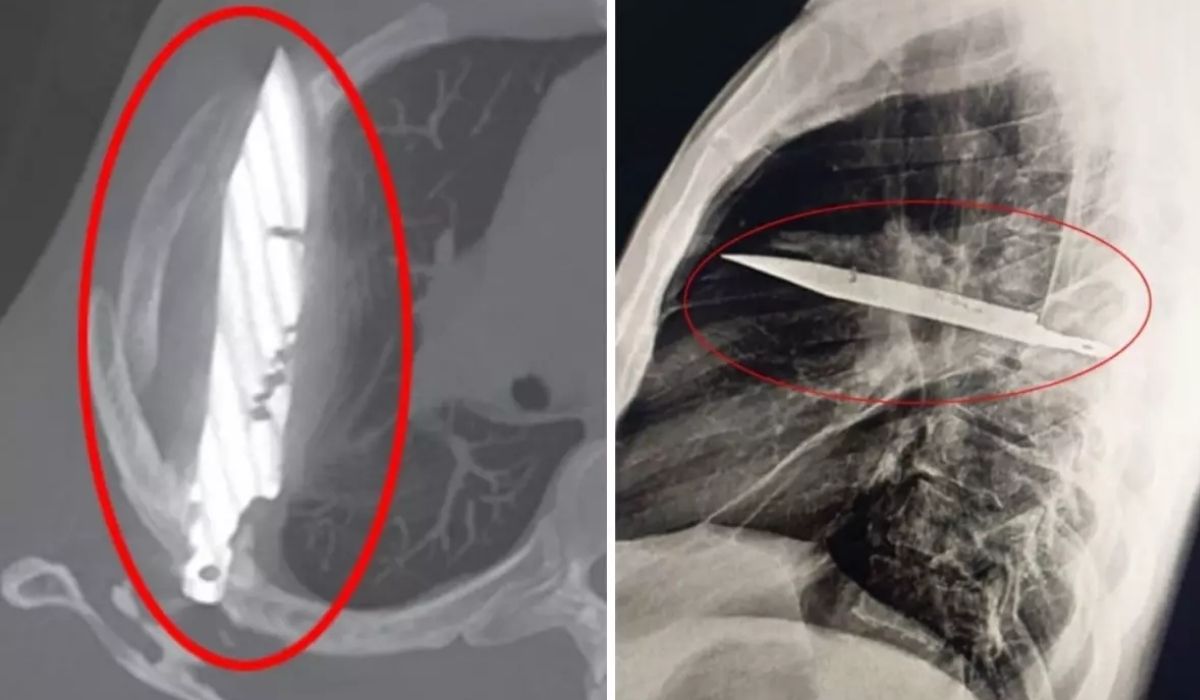

Tanzanya’da 44 yaşındaki bir adam, sağ memesinin altından iltihap akması şikâyetiyle hastaneye gitti. Doktorlar ilk muayenede herhangi bir ağrı, nefes darlığı, öksürük ya da ateş bulgusuna rastlamadı. Ancak yapılan röntgen, herkesin ağzını açık bıraktı: Adamın göğsünde tam sekiz yıldır saplı duran bir bıçak vardı.

Bıçak, sağ kürek kemiğinden girip hayati organlara zarar vermeden göğsünde kalmıştı. Ameliyatla çıkarılan bıçakla birlikte ölü doku temizlendi. Hasta yoğun bakımda bir gün, normal serviste ise 10 gün kaldı. Doktorlar, takip kontrollerinde hastanın tamamen iyileştiğini duyurdu.